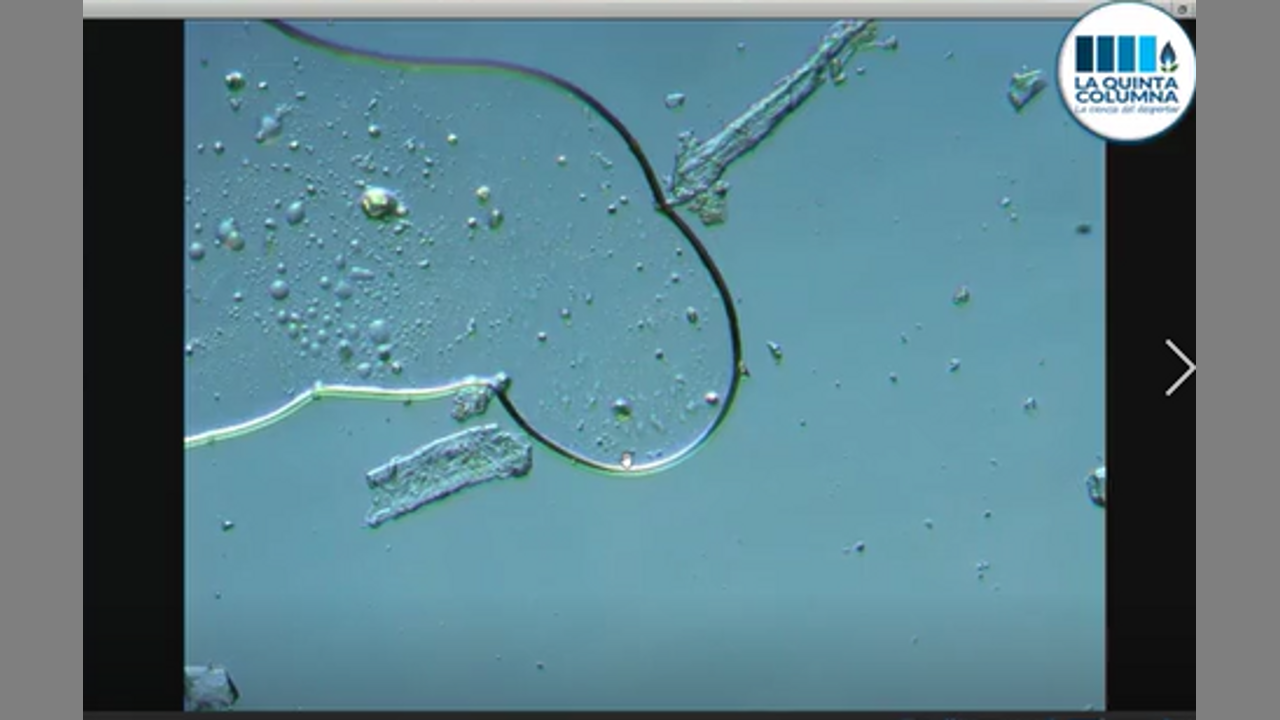

EN DIRECTO ANÁLISIS DE UNA GOTA DE INYECTABLE ANESTÉSICO ULTRACAIN USADO EN CLINICAS DENTALES